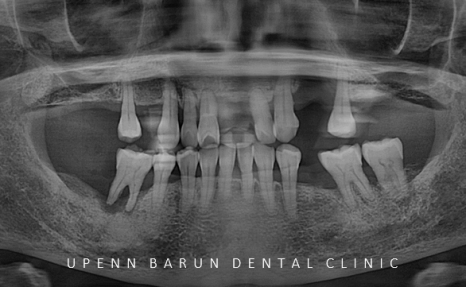

오른쪽 : 초진 파노라마

엑스레이와 함께 초진을 해보니

흔들리는 치아가 많이 있었으며

치주염으로 인해 치아들이 많이 정출되어 있었고,

어금니쪽에서 지지를 해 주지 못해

앞니끼리도 과도하게 맞물리고 있는 상태였습니다.